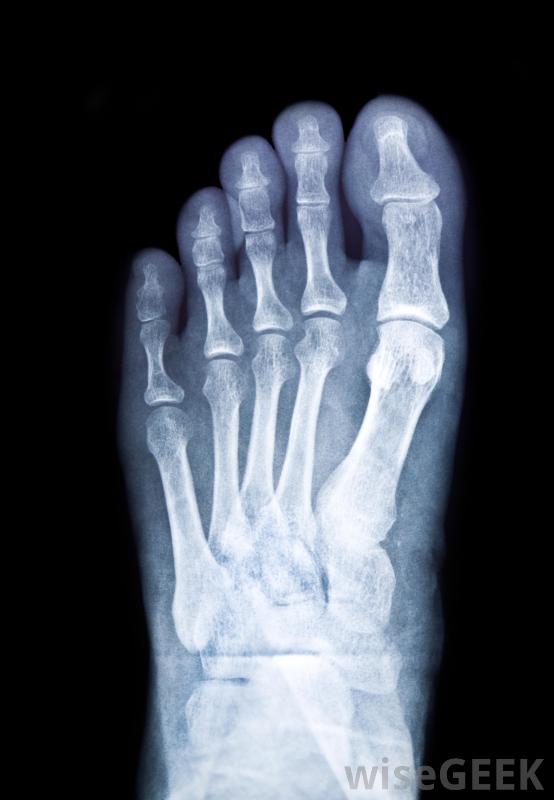

足踝外科医生对脚和踝关节进行外科手术。这可能包括重建手术和整容手术。足踝外科医生的一些手术也可能包括矫正足部畸形和修复外伤如果出现多处骨折,外科医生在手术前可能需要做一次足部x光片。有一些特殊的设施,比如足踝诊所,训练有素的专家在那里治疗他们的病人。足科医生或足部外科医生可以检查和治疗这些诊所的病人。诊所可以为不预约的病人提供治疗,这对某些人来说更方便。脚后跟疼痛有时表明需要进行足部手术足踝外科医生可能要做的一些主要手术是治疗因受伤引起的骨折。脚趾骨折、脚踝骨折或足部骨折可能需要手术来修复。这通常被称为矫形外科手术。一些足踝专家治疗所有年龄段的人,还有一些专门从事儿科护理对于足部缓慢愈合的伤口,需要切除坏死组织的外科手术可能是一种治疗方法,医生可以对脚后跟进行x光检查以确定病因。如果有严重骨折或足跟骨刺无法通过其他疗程进行矫正,则可将患者转诊给足踝外科医生。患者可能有开放性、闭合性或移位性跟骨骨折,外科医生可以通过手术进行修复。手术对于恢复足部的完整功能和避免以后的并发症是必要的。这些手术可能涉及骨骼平滑或移植。X光片可用于确定脚跟疼痛的原因。车祸或跌倒等事故可能会导致脚部或踝部受伤。可能会请足踝外科医生或专家来评估情况。如果脚或踝关节有骨折或压碎的骨头,外科医生可能需要通过外科手术来修复损伤。移除碎块或碎骨是一种手术方法。可能还需要插入金属针来固定骨头前脚或脚趾的应力性骨折是足踝外科医生可能治疗的一种损伤。如果出现多处骨折或脚趾看起来有脱臼,外科医生可能需要进行骨扫描和x光检查。他可能会在手术前尝试减轻肿胀一名高级足踝外科医生可以利用他所在领域的最新技术和技术进步来治疗病人。他通常获得董事会认证,专门从事足踝重建手术。他还可以治疗特殊需要的病例,例如糖尿病并发症导致的足部伤口。在缓慢愈合的足部伤口中,需要切除坏死组织的外科手术可能是一种治疗方法。扁平足的病人可以转诊给足踝外科医生或专科医生。外科医生可以进行一种包括植入用于重新定位脚和脚踝的装置。这将使行走时有更大的运动和放松。脚踝骨折的人。